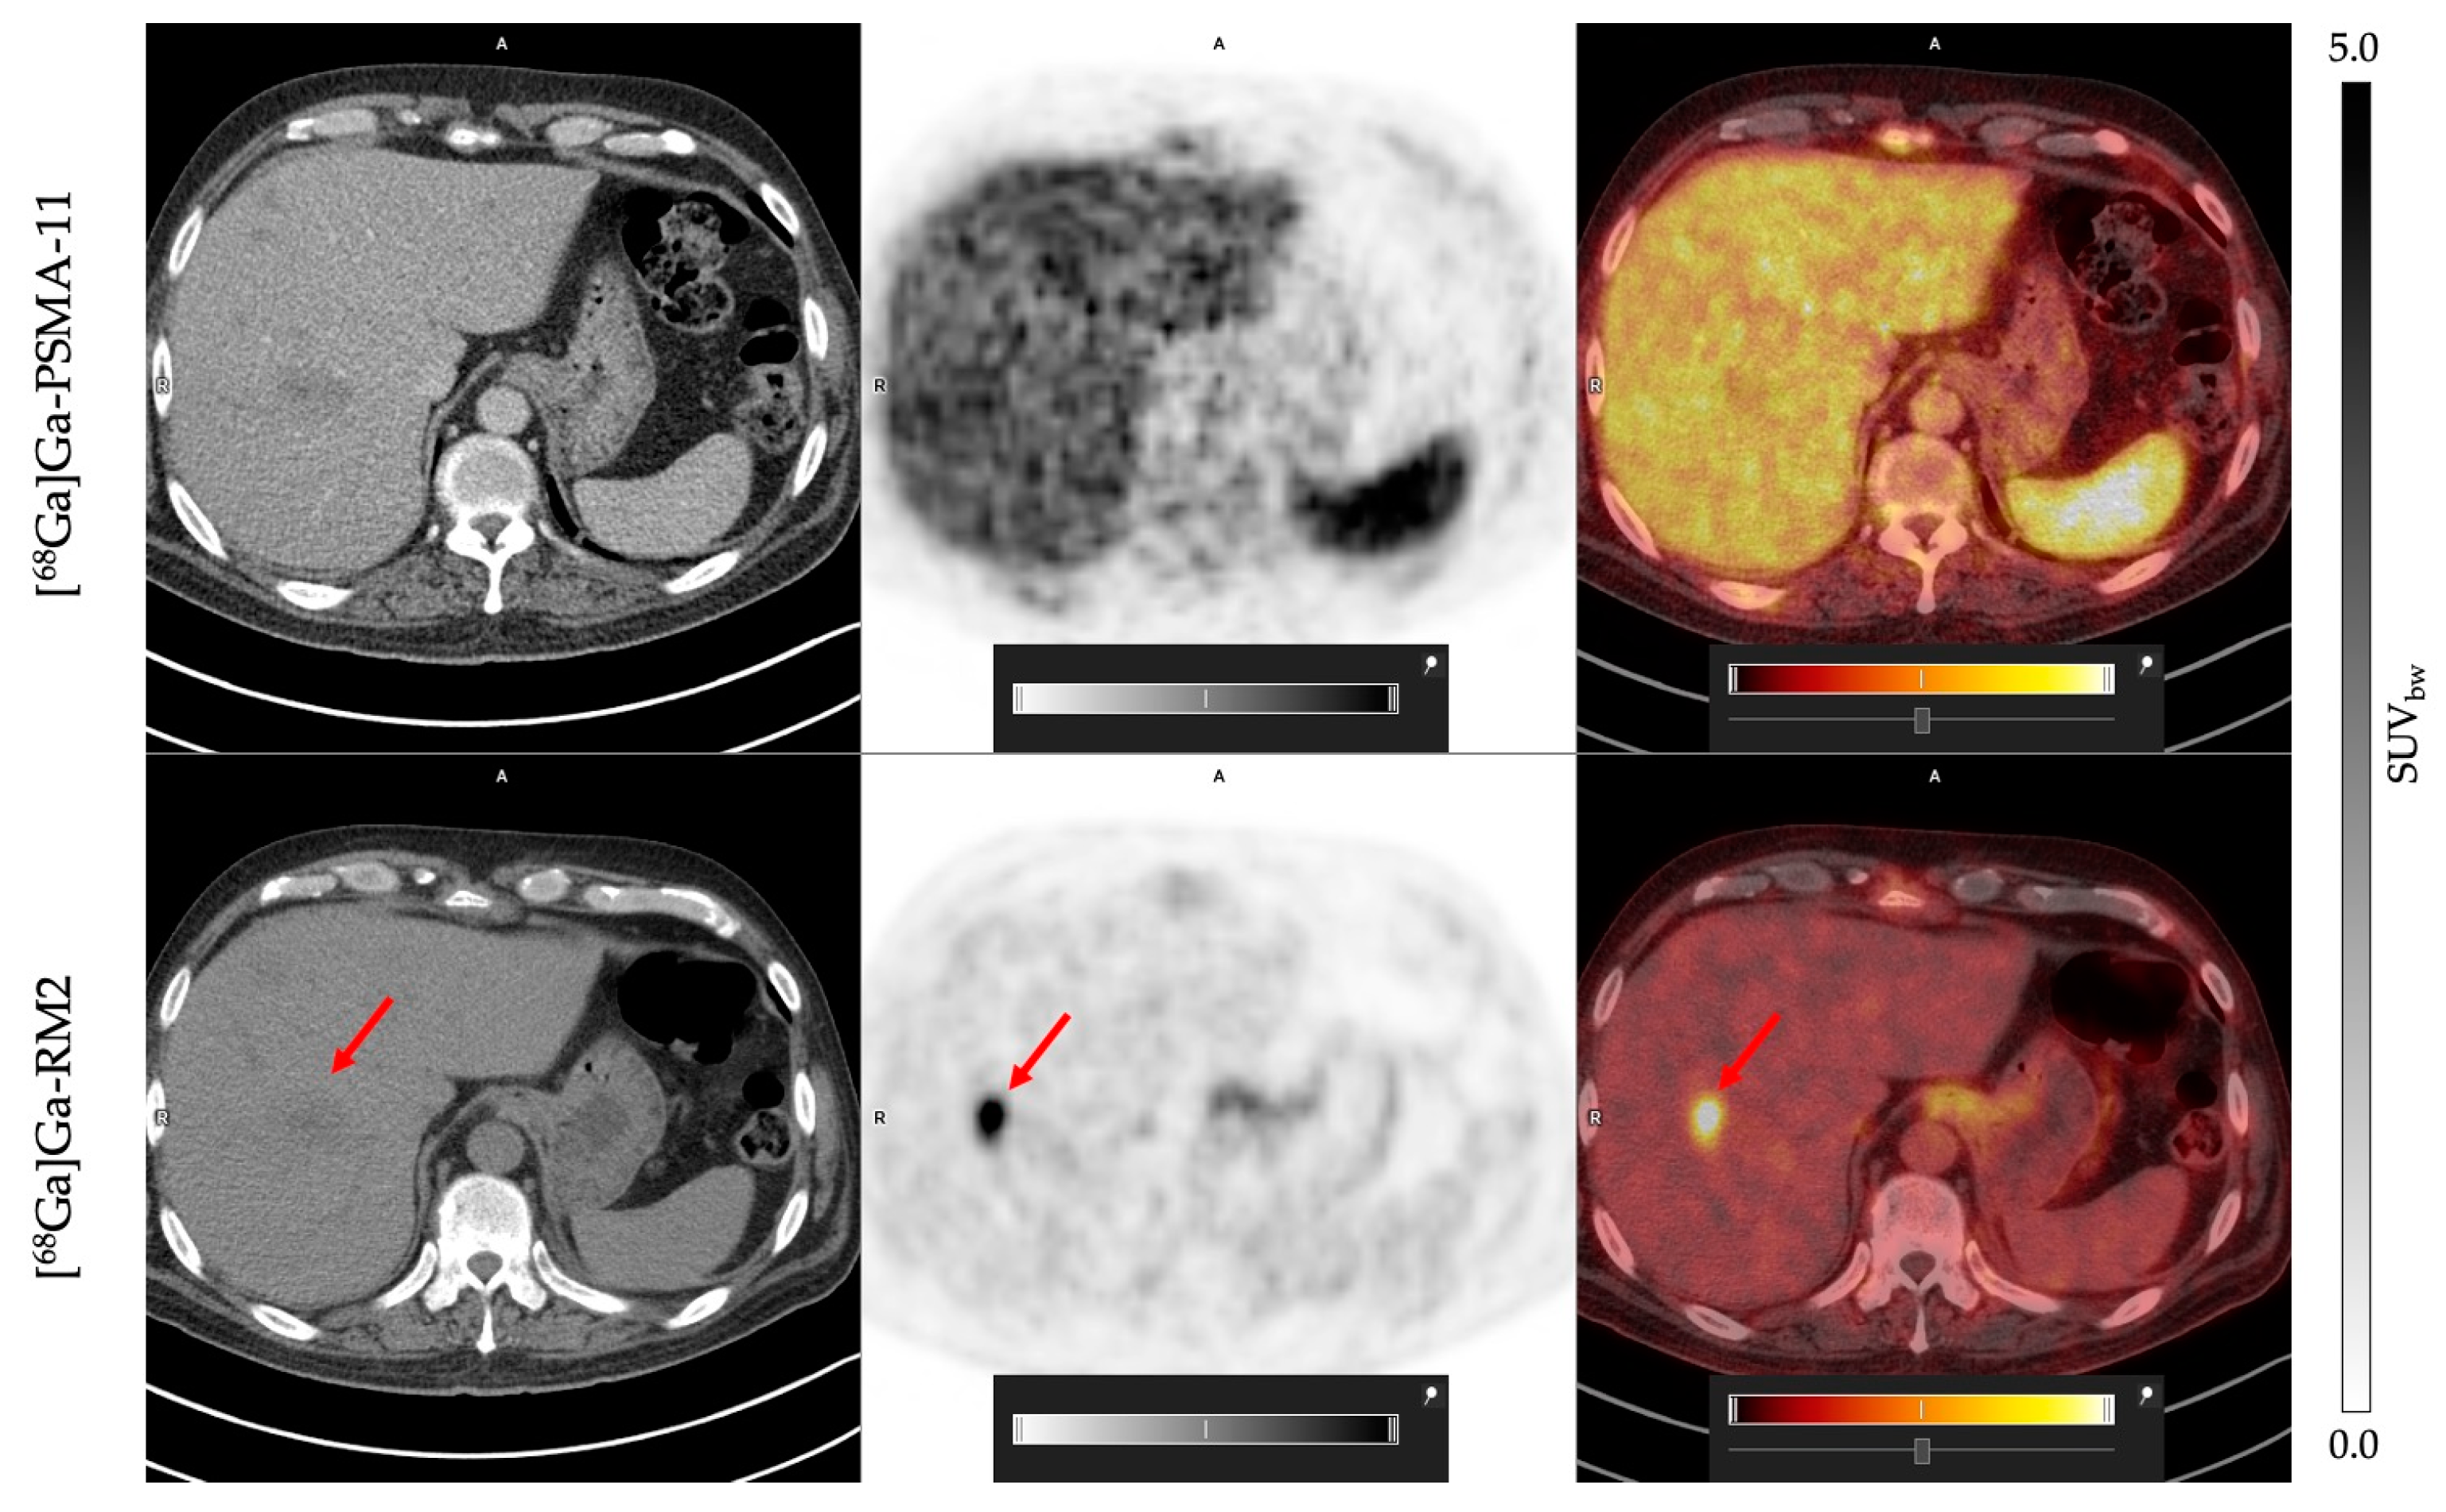

[68Ga]Ga-RM2 presents an absence of physiological uptake in the liver, contrary to what was observed with [68Ga]Ga-PSMA-11, which favors the detection of possible hepatic metastasis lesions. This was validated in one patient, who exhibited a hepatic lesion with [68Ga]Ga-RM2 that was not visible on [68Ga]Ga-PSMA-11 scan (Figure 3).

Figure 3.

Patient 13: PET/CT [68Ga]Ga-PSMA-11 (upper row) and [68Ga]Ga-RM2 (lower row). Red arrows indicates a liver metastasis visible with [68Ga]Ga-RM2 and not detected with [68Ga]Ga-PSMA-11.

We and others have shown that PSMA is highly expressed in prostate tumoral lesions and also in kidneys, spleen, lacrimal, parotid, and submandibular glands, small intestine, and bladder [14,40,53]. This is consistent with what we observed in the present study. The physiological expression of GRPr shows a different pattern compared to PSMA and is high in the pancreas, bladder [14], lymph node metastases, and bone lesions of prostate cancer [11]. Interestingly, the low uptake of [68Ga]Ga-RM2 in hepatic tissue allowed the detection of a malignant lesion in the liver, while this lesion was not observed in the [68Ga]Ga-PSMA-11 PET/CT scan (Figure 4). This observation is in line with results reported by Verhoeven et al. (2023) [54].